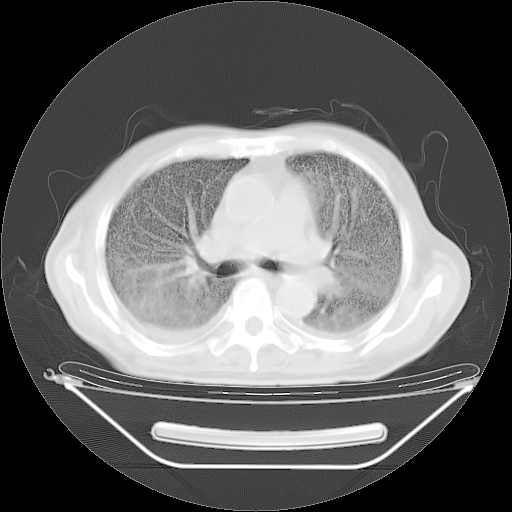

今天复查肺部CT,发现双肺广泛磨玻璃样改变。所以我把3月19日和5月9日相隔50天的肺部CT上传。请大家会诊。

2009年3月19日肺部CT片。

5月9日肺部CT(在4月27日齐鲁医院肺部CT描述部分肺组织磨玻璃样改变,12天后肺组织广泛磨玻璃样改变)